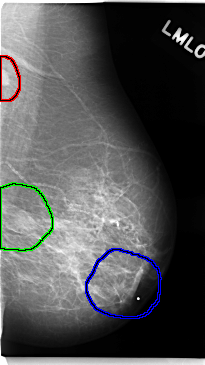

C_0146_1.LEFT_MLO

FILE: C_0146_1.LEFT_MLO.OVERLAY

TOTAL_ABNORMALITIES 3

ABNORMALITY 1

LESION_TYPE MASS SHAPE OVAL MARGINS CIRCUMSCRIBED

ASSESSMENT 5

SUBTLETY 5

PATHOLOGY MALIGNANT

TOTAL_OUTLINES 1

BOUNDARY

ABNORMALITY 2

LESION_TYPE MASS SHAPE LOBULATED MARGINS ILL_DEFINED

ASSESSMENT 4

SUBTLETY 4

ABNORMALITY 3

LESION_TYPE MASS SHAPE IRREGULAR MARGINS ILL_DEFINED